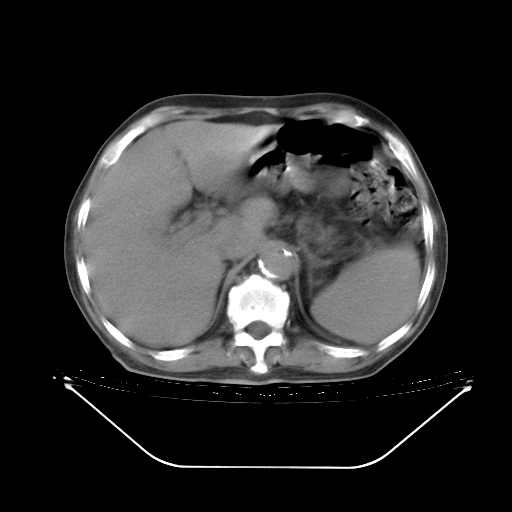

今天复查肺部CT,发现双肺广泛磨玻璃样改变。所以我把3月19日和5月9日相隔50天的肺部CT上传。请大家会诊。

5月9日肺部CT(在4月27日齐鲁医院肺部CT描述部分肺组织磨玻璃样改变,12天后肺组织广泛磨玻璃样改变)

2009年5月9日肺部CT

大致读了系列胸部CT:纵隔窗无明显异常,肺窗:从4、27至今:主要是双肺中下野外带可见毛玻璃样改变,目前处于急性肺泡炎阶段,至于原因考虑1、结替组织或胶原血管性疾病所致?2、恶性疾病如恶组在肺部所致的表现或细支气管肺泡癌?3、药物或其它原因如肺蛋白沉着症所致肺泡炎目前不太可能?总之,明天就去请我院的呼吸科、感染科、血液科和临免专家会诊哈。